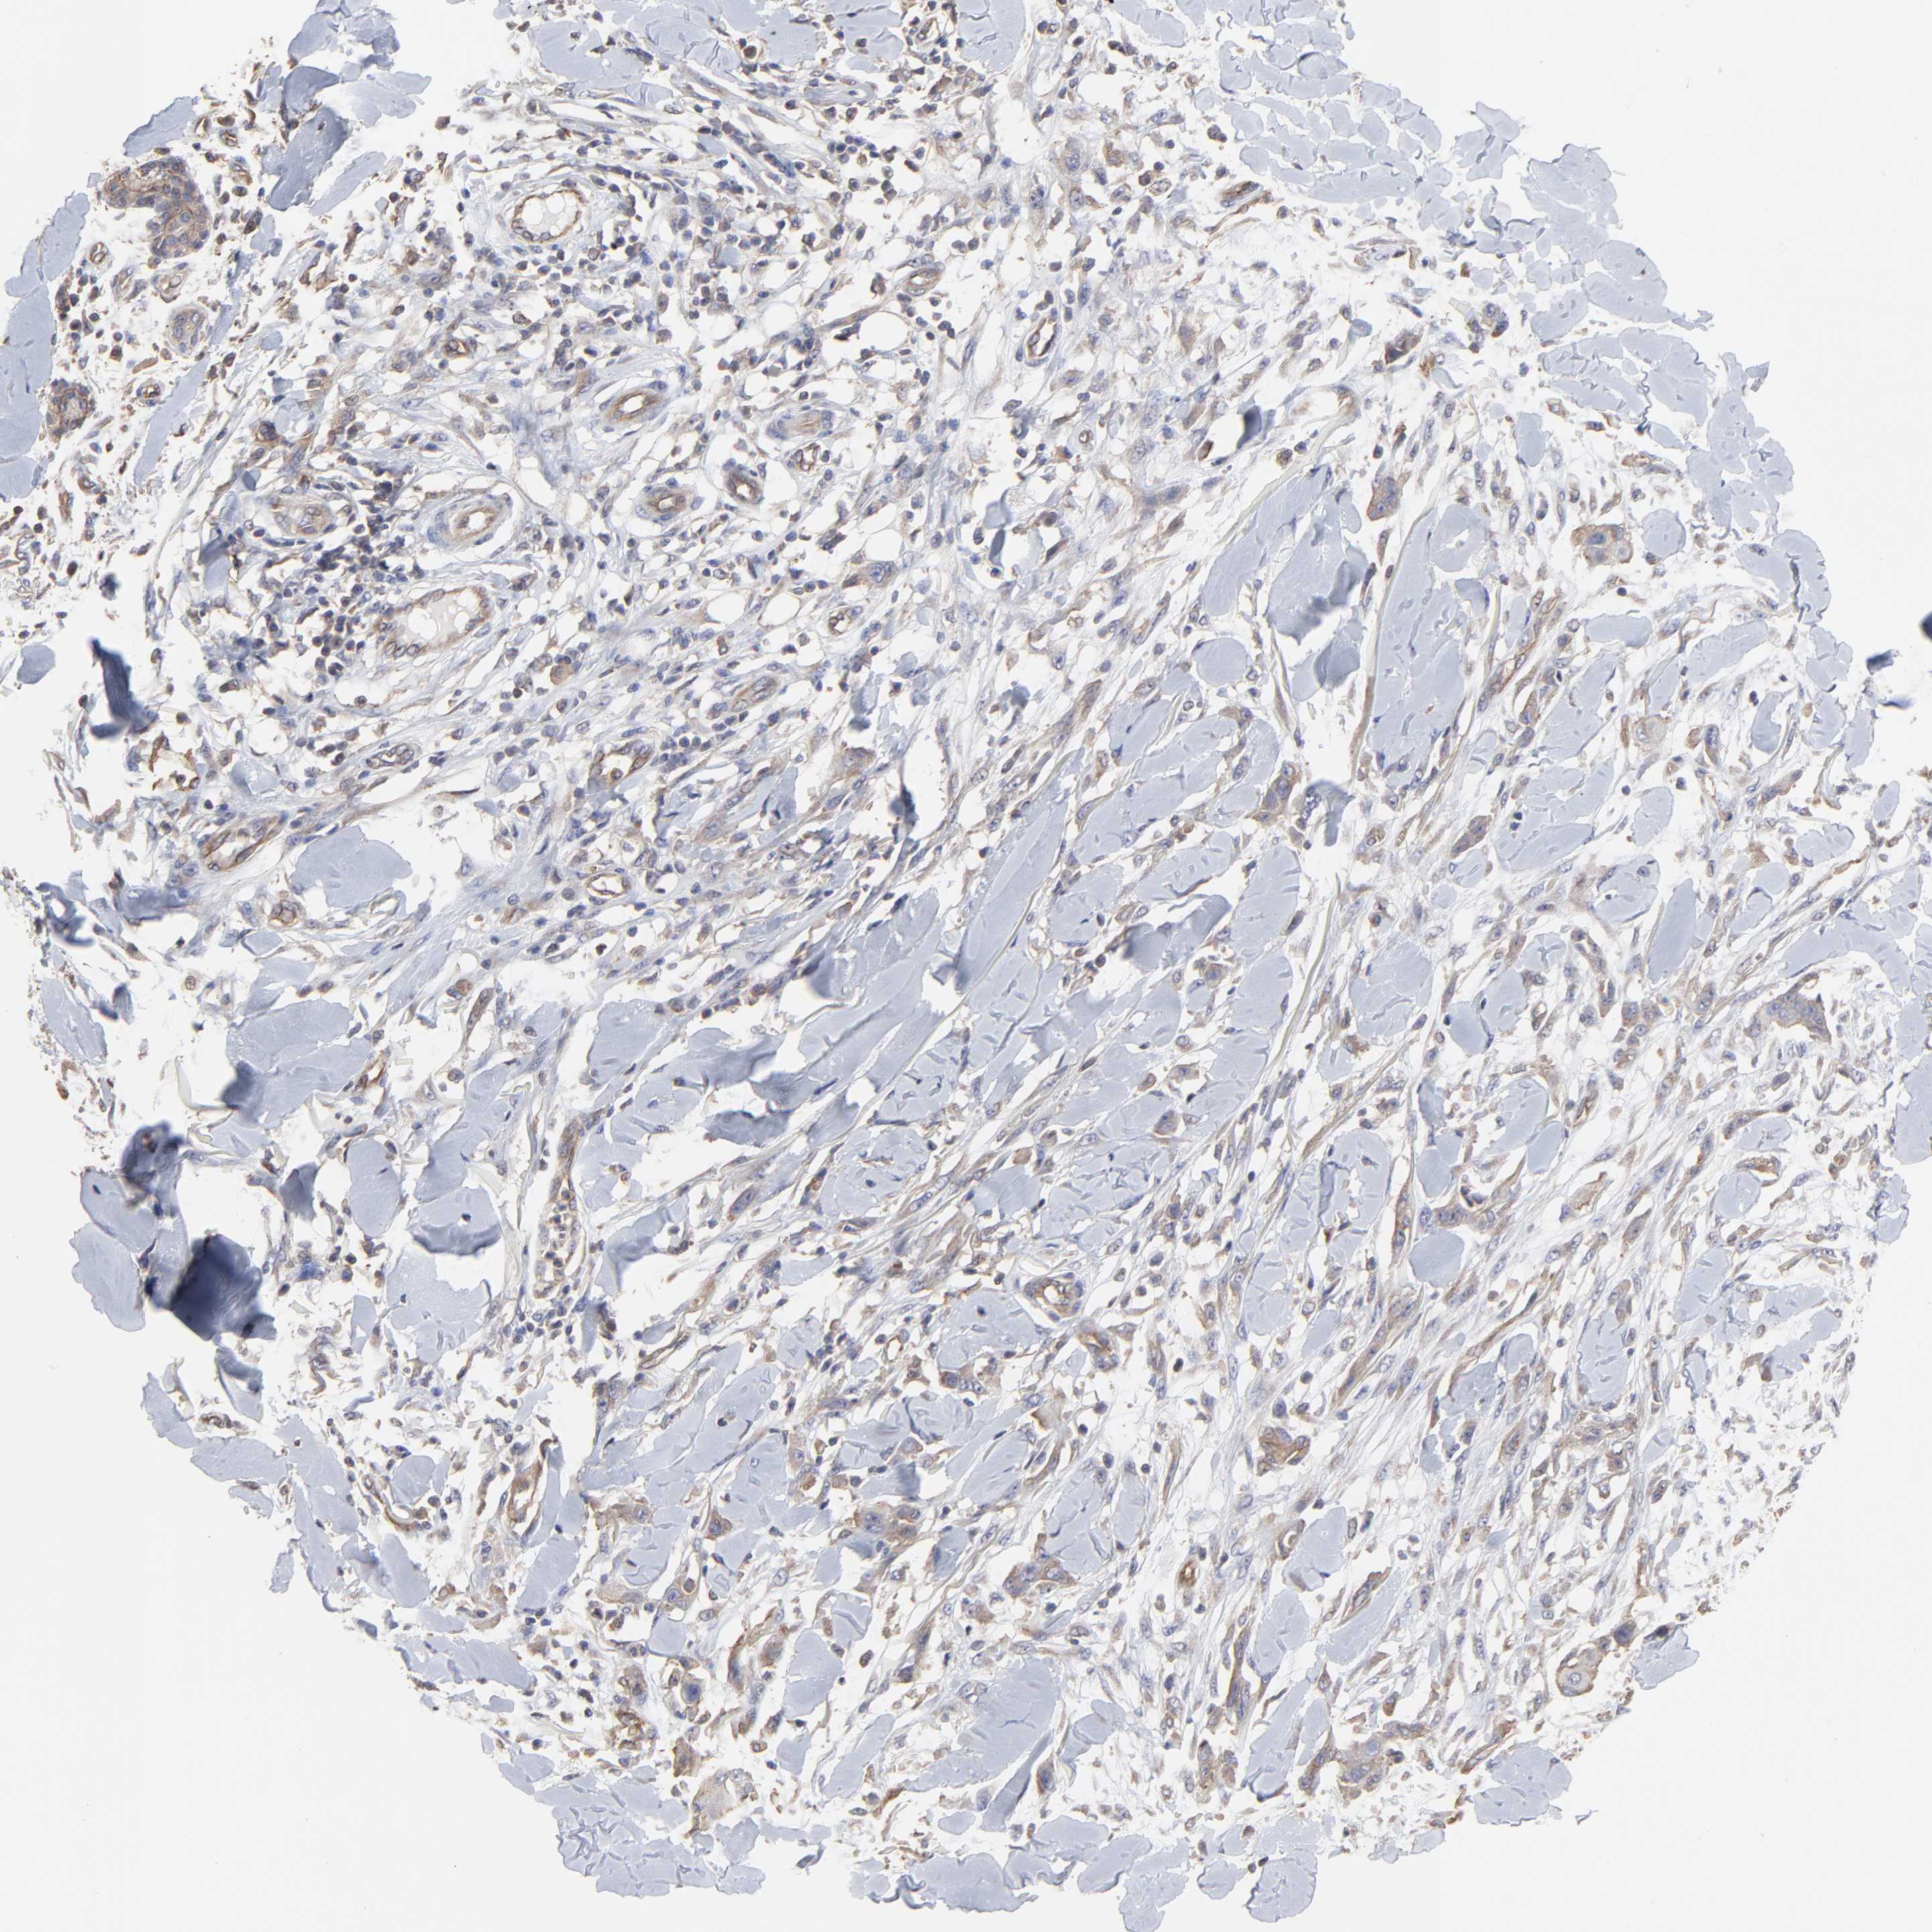

SKIN CANCER - Protein expressioni

A mouse-over function shows sample information and annotation data. Click on an image to view it in a full screen mode. Samples can be filtered based on level of antibody staining by selecting one or several of the following categories: high, medium, low and not detected. The assay and annotation is described here.

Antibody stainingi

Antibody staining in the annotated cell types in the current human tissue is reported as not detected, low, medium, or high, based on conventional immunohistochemistry profiling in selected tissues. This score is based on the combination of the staining intensity and fraction of stained cells.

Each image is clickable and will lead to virtual microscopy that enables deeper exploration of all samples and also displays staining intensity scores, fraction scores and subcellular localization as well as patient and tissue information for each sample.

Antibody HPA003004

Squamous cell carcinoma, NOS

Basal cell carcinoma

Squamous cell carcinoma in situ, NOS

Squamous cell carcinoma, metastatic, NOS